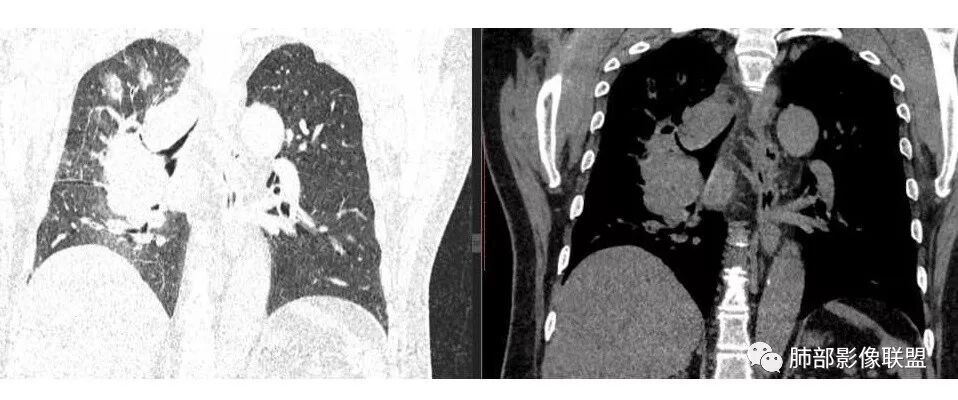

张帅: 患者以肢体无力就诊,既往有吸烟史,胸CT:右肺门占位性病变,密度不均,病灶内病灶内支气管明显狭窄,走行僵硬,病灶边缘光滑,呈浅分叶,未见明显毛刺,对中叶支气管明显挤压。右肺内可见散在片状实变影,前纵隔淋巴结明显肿大,内可见低密度区,2r 4r 7 10r淋巴结明显肿大。诊断考虑恶性方向,肺癌(小细胞)并纵隔肺门淋巴结转移?淋巴瘤?

水晶石头: 患者中老年男性,以四肢乏力为症状表现,有吸烟史。胸部CT:右肺上叶不规则结节,周围见磨玻璃影,小叶间隔增厚。同侧纵膈明显淋巴结肿大。综合考虑恶性。存在小病灶大转移,冰冻纵隔,且有内分泌症状,首先小细胞癌可能大。监测排外淋巴瘤。

肺门及纵隔多发淋巴结。2L,4R,3区都有肿大淋巴结。

局限性中央间质增厚,考虑癌性淋巴管炎

1.右肺上叶不规则结节影,右肺门及纵隔多结节并形成巨大块影,密度均匀,沿途支气管明显狭窄。

原发灶小或隐匿,肺门纵隔淋巴结异常增大,所谓“娘小崽大”常见于肺小细胞癌!

2.右肺小叶间隔增厚伴微小结节,提示癌性淋巴管炎。